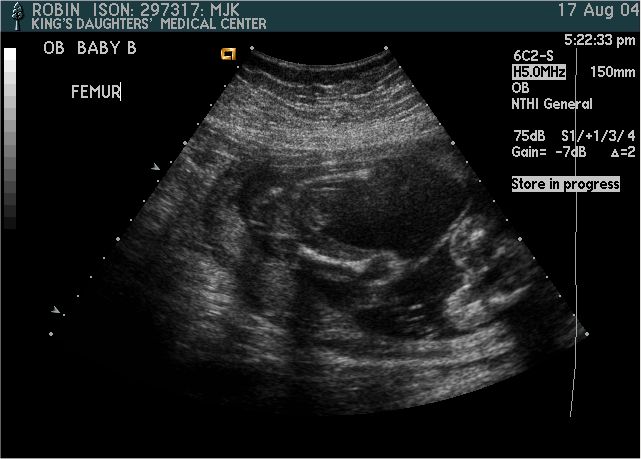

Baby B

Pictures from Ultrasound at 20 weeks.